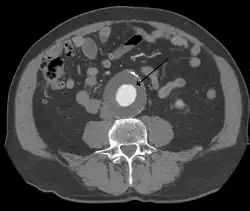

The diagnosis of an abdominal aortic aneurysm can be confirmed by the use of ultrasound. Rupture may be indicated by the presence of free fluid in the abdomen. A contrast-enhanced abdominal CT scan is the best test to diagnose an AAA and guide treatment options.[14]

A large, rapidly expanding, or symptomatic aneurysm should be repaired, as it has a greater chance of rupture. Slowly expanding aortic aneurysms may be followed by routine diagnostic testing (i.e., CT scan or ultrasound imaging).

For abdominal aneurysms, the current treatment guidelines for abdominal aortic aneurysms suggest elective surgical repair when the diameter of the aneurysm is greater than 5 cm (2 in). However, recent data on patients aged 60–76 suggest medical management for abdominal aneurysms with a diameter of less than 5.5 cm (2 in).[31]